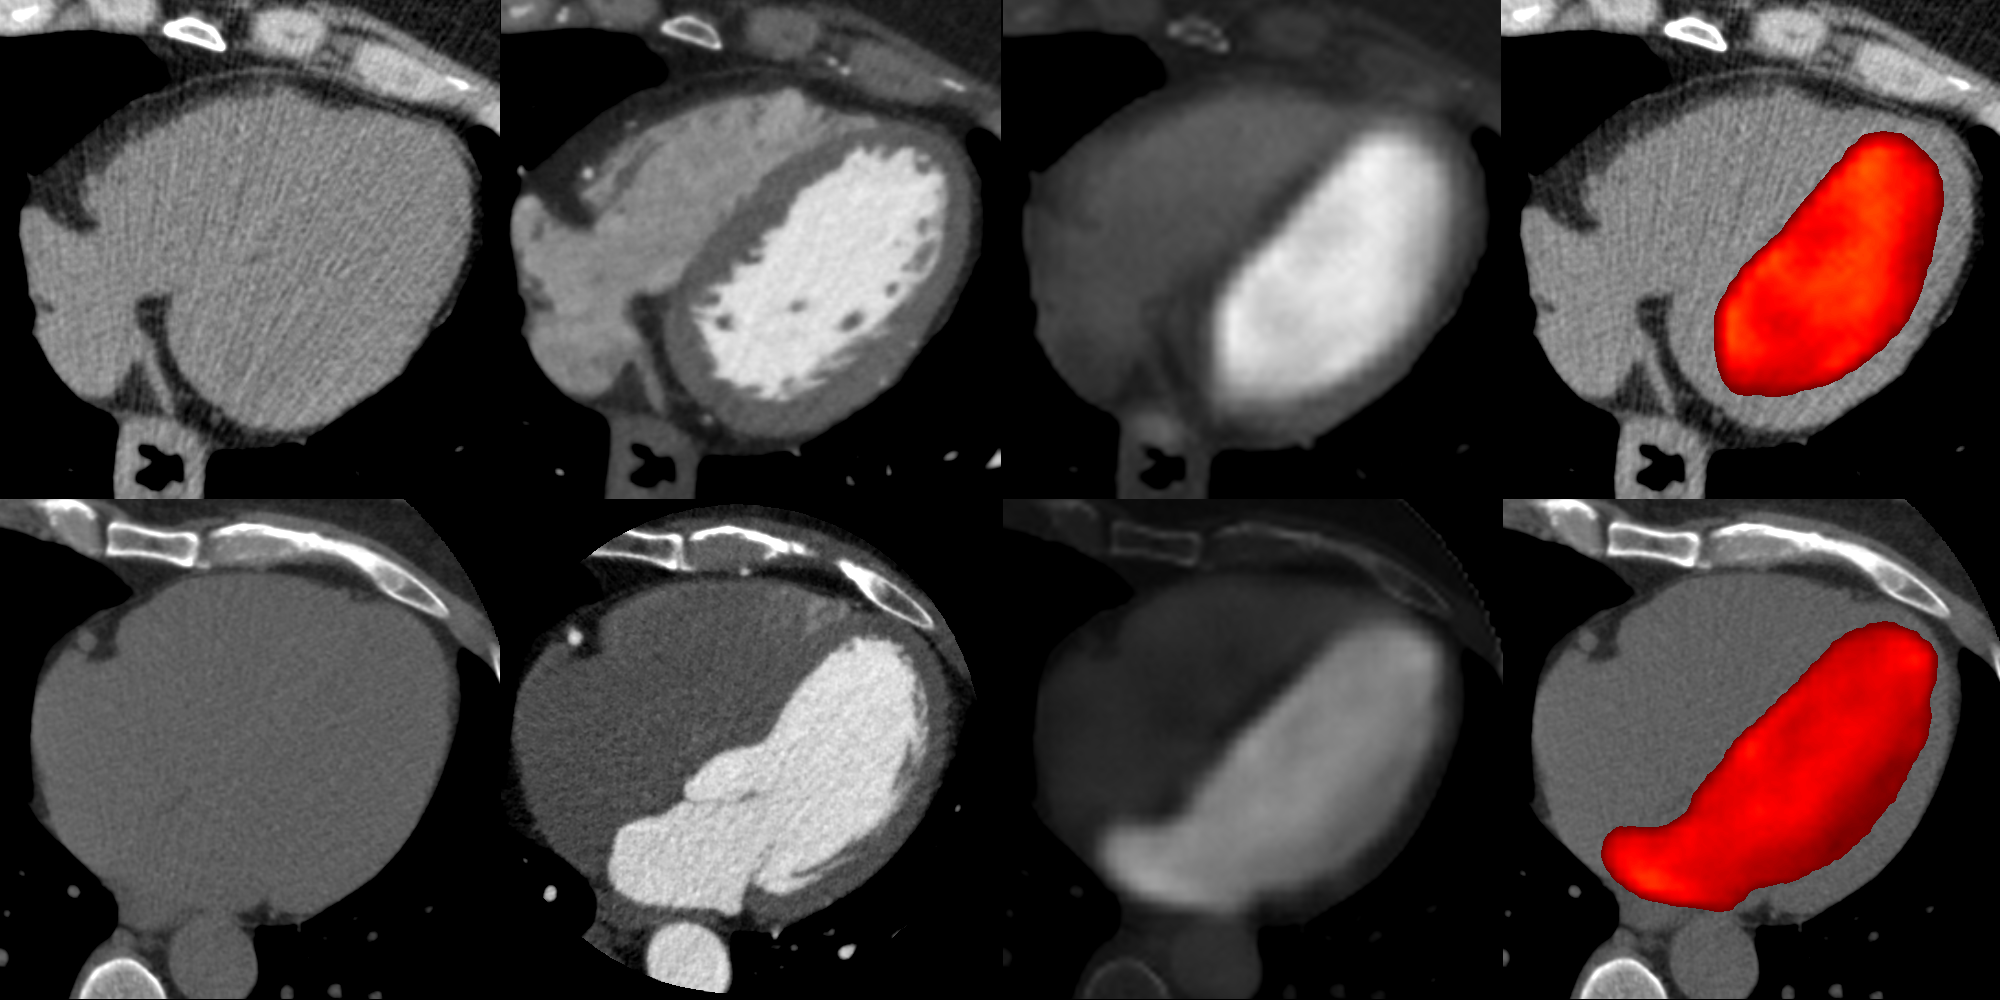

Refer to caption

Figure 4: Two examples of image synthesizing. From left to right: the contrast free CT image, the real CECT image, the synthesized CECT image and the fusion of the basal CT image with the estimated chambers.

The synthetic CECT images show a good similarity and contrast dynamics (NMI=0.93±0.03𝑁𝑀𝐼plus-or-minus0.930.03NMI=0.93\pm 0.03, PSNR=48.30±2.03𝑃𝑆𝑁𝑅plus-or-minus48.302.03PSNR=48.30\pm 2.03) compared to the gold standard (i.e a real CECT images), allowing a simple extraction of the left cardiac chambers by thresholding. The comparison of the automatic segmentation with the manual reference annotations highlights an independence of the synthesized chambers morphology from both the heart shapes and the slice positions in the CT volume (Dice=0.88), Fig.4.